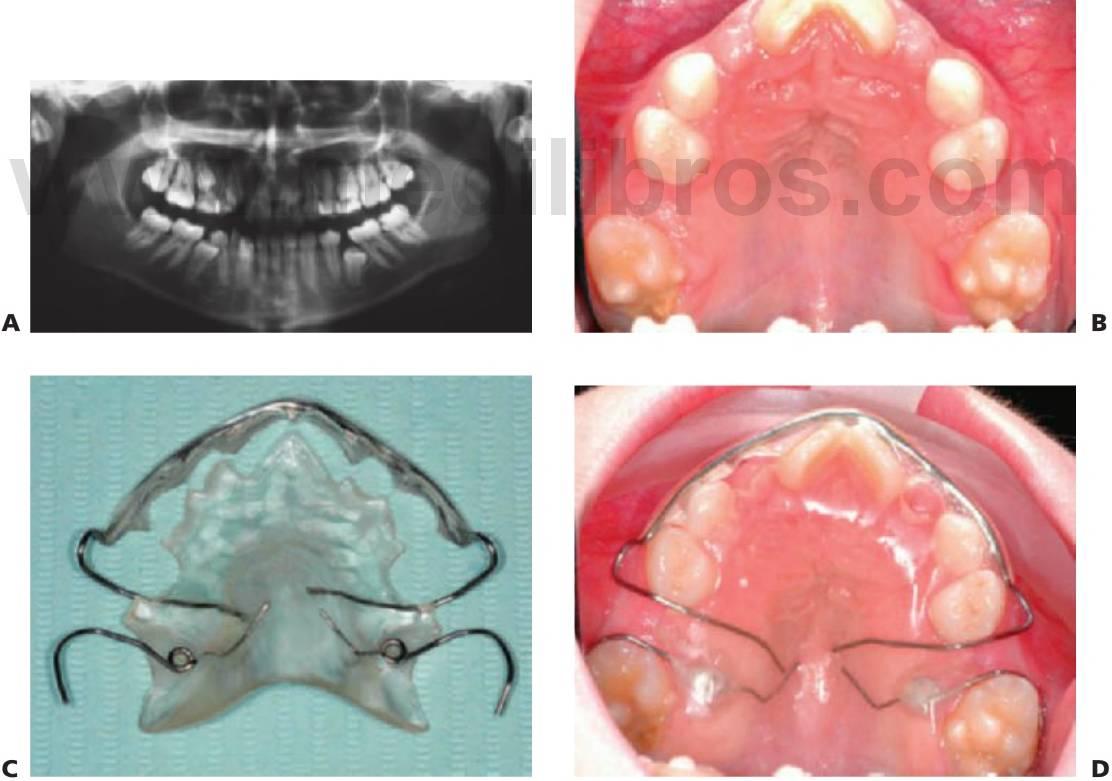

Expansión maxilar lenta: quad hélix/expansores de níquel-titanio

El quad hélix se ajusta a las bandas molares que se cementan en los primeros molares permanentes.

El dentista controla la activación del aparato.

La reactivación se realiza en visitas alternas y se puede realizar de forma intraoral mediante el uso de un alicate de tres puntas o extrayendo el aparato de la boca y realizando la expansión a mano.

La expansión debería proseguir hasta sobrecorregir los molares y se mantendría el aparato de esa forma durante 3 meses más. Así, la mordida cruzada suele corregirse en 4-6 meses.

El quad hélix puede utilizarse al mismo tiempo que la aparatología fija.

Los expansores de níquel-titanio precisan menos ajuste que los quad hélix convencionales de acero inoxidable.

Producen una cantidad predeterminada de expansión.

El enfriamiento del expansor permite constreñirlo e insertarlo en los tubos linguales de los molares superiores.

Cuando se calienta a la temperatura corporal, se convierte en elástico y ejerce una fuerza continua en los dientes que provoca la expansión de arco.

Las fuerzas de expansión producen también la desrotación simultánea de los molares (figs. 11.14, 11.15).